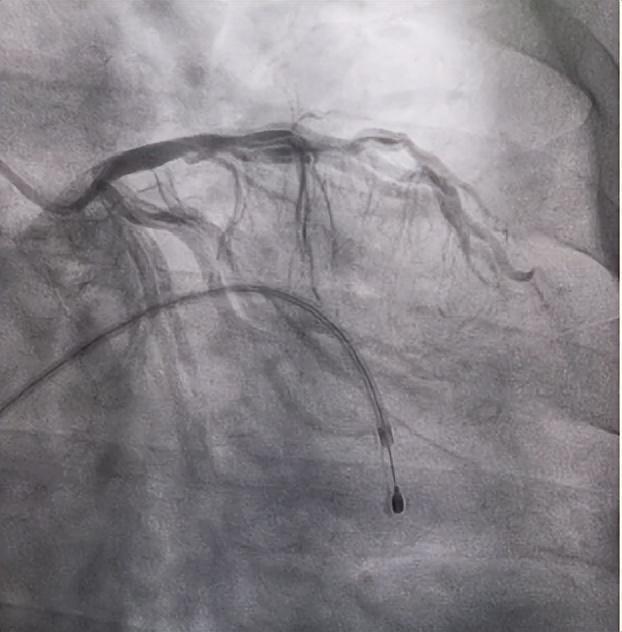

梁师傅进入导管手术室后,心血管内科团队立即安排放置临时起搏器和冠脉造影。造影显示给心肌主要供血的右冠状动脉完全闭塞,左冠状动脉细小。医生立即实施开通血管方案,为患者进行“经皮冠脉腔内成形术”,手术顺利完成,患者转危为安。